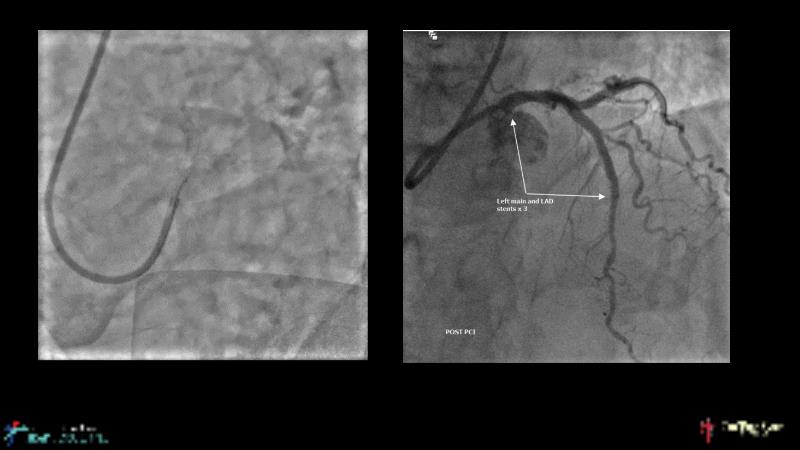

This session is recommended for you if you are seeking insights into the advantages of using IVUS imaging over visual assessment for better outcomes in left main bifurcation procedures. Discuss with experts the benefits of using RotaCUT in lesion preparation for left main bifurcation and explore the impact of high radial strength stents on the procedure's success.

• To know how a high radial strength stent can make a difference in left main bifurcation